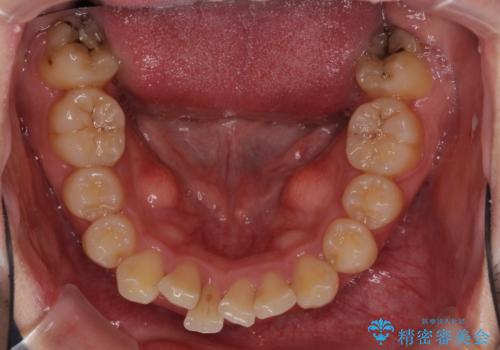

強い咬み込みですり減った前歯 デコボコを抜歯矯正で整える

咬合力が非常に強く、抜歯したスペースがなかなか閉じないであろうことは予想できましたが、思っていた以上に期間がかかりました。

前歯のすり減りも著しかったため、仕上げの位置の調整にも期間を要しました。